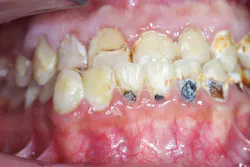

Patient: 24-year-old male with HbSS SCD, renal insufficiency, and frequent vaso-occlusive crises (figure 1)

Chief complaint: Pain, sensitivity, and desire for improved esthetics

Findings

- Rampant caries, pulpal involvement, enamel hypoplasia

- Gingival pallor and mild inflammation

- Facial esthetic concerns and malocclusion